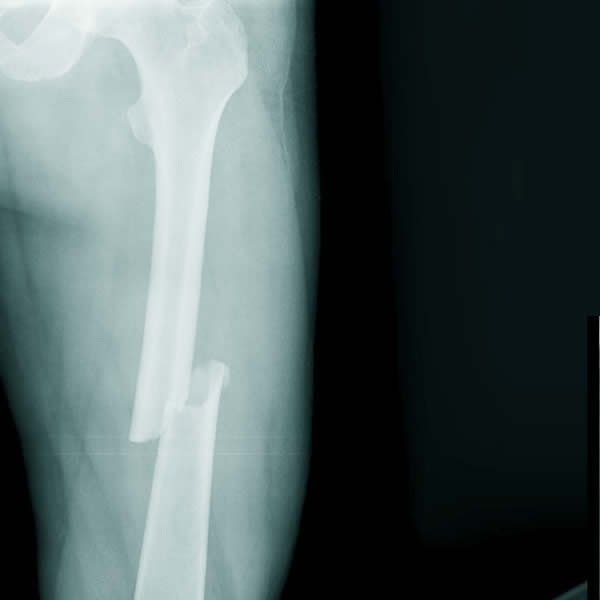

Xương đùi là phần xương chắc khỏe nhất trong cơ thể vì thế phải có lực tác động rất mạnh mới có thể làm gãy thân xương đùi. Xương đùi cũng là xương dài nhất, mỗi vị trí gãy sẽ có đặc điểm và biện pháp xử trí khác nhau.

Qua hình ảnh X-quang có thể xác định vị trí, hình thái của ổ gãy. Về vị trí, có thể dựa vào đặc điểm giải phẫu để xác định. Vị trí dễ bị gãy nằm ở 1⁄3 trên, giữa hoặc dưới của đoạn xương. Về hình thái, xác định được đường gãy của xương là gãy ngang, gãy chéo vát, gãy bong sụn tiếp hợp, gãy phạm khớp, hay gãy cành xanh, gãy lún.